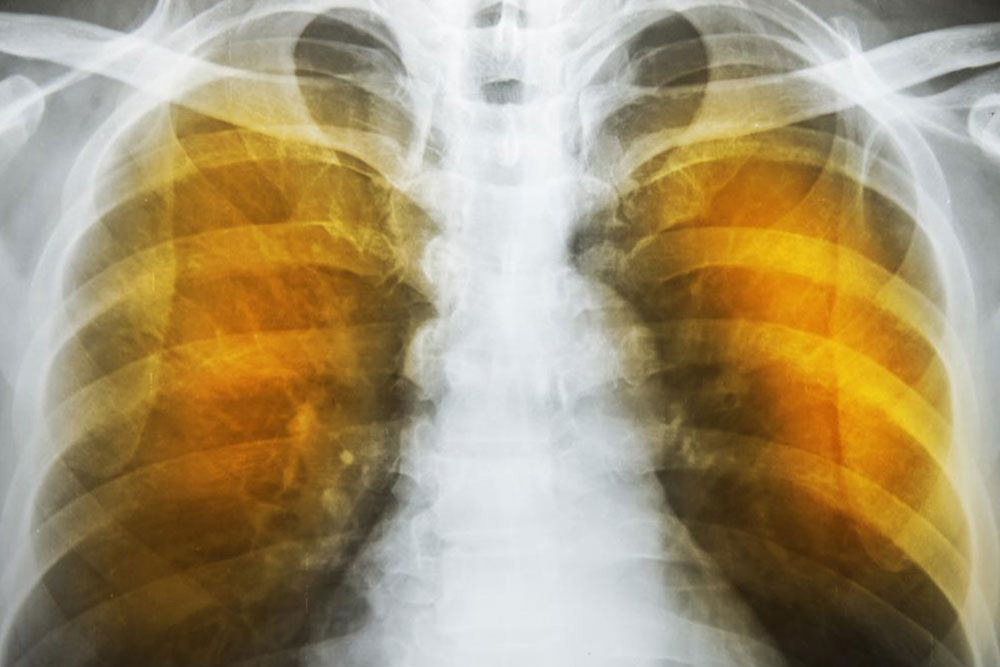

What is emphysema and what are its complications?

Emphysema is an oppressive respiratory disorder which results from the disintegration of the alveoli, i.e., the tissues where the interchange of gas with blood takes place. Destruction in any large scale will reduce the gas transfer area and the process of gas transfer itself, leading to oxygen starvation or hypoxia. When conventional treatment with bronchodilators, corticosteroids etc. have ceased to give relief, one has to resort to a method known as Long Term Oxygen Therapy or LTOT.

Another complication is the alveoli becoming weaker, and then starting to break. When this assumes larger scale, vacant spaces are formed called bullae. This reduces the gas transfer area as well as the capacity of the lung to expand. These are often have to be surgically removed to allow more space for the lung to expand. In the ultimate case, lung transplant becomes the only choice. Another scenario is a large-scale disintegration of alveoli that can cause pneumothorax, which is a condition in which the chest cavity is filled with air and the lungs collapse. This is a very serious condition if not fatal.